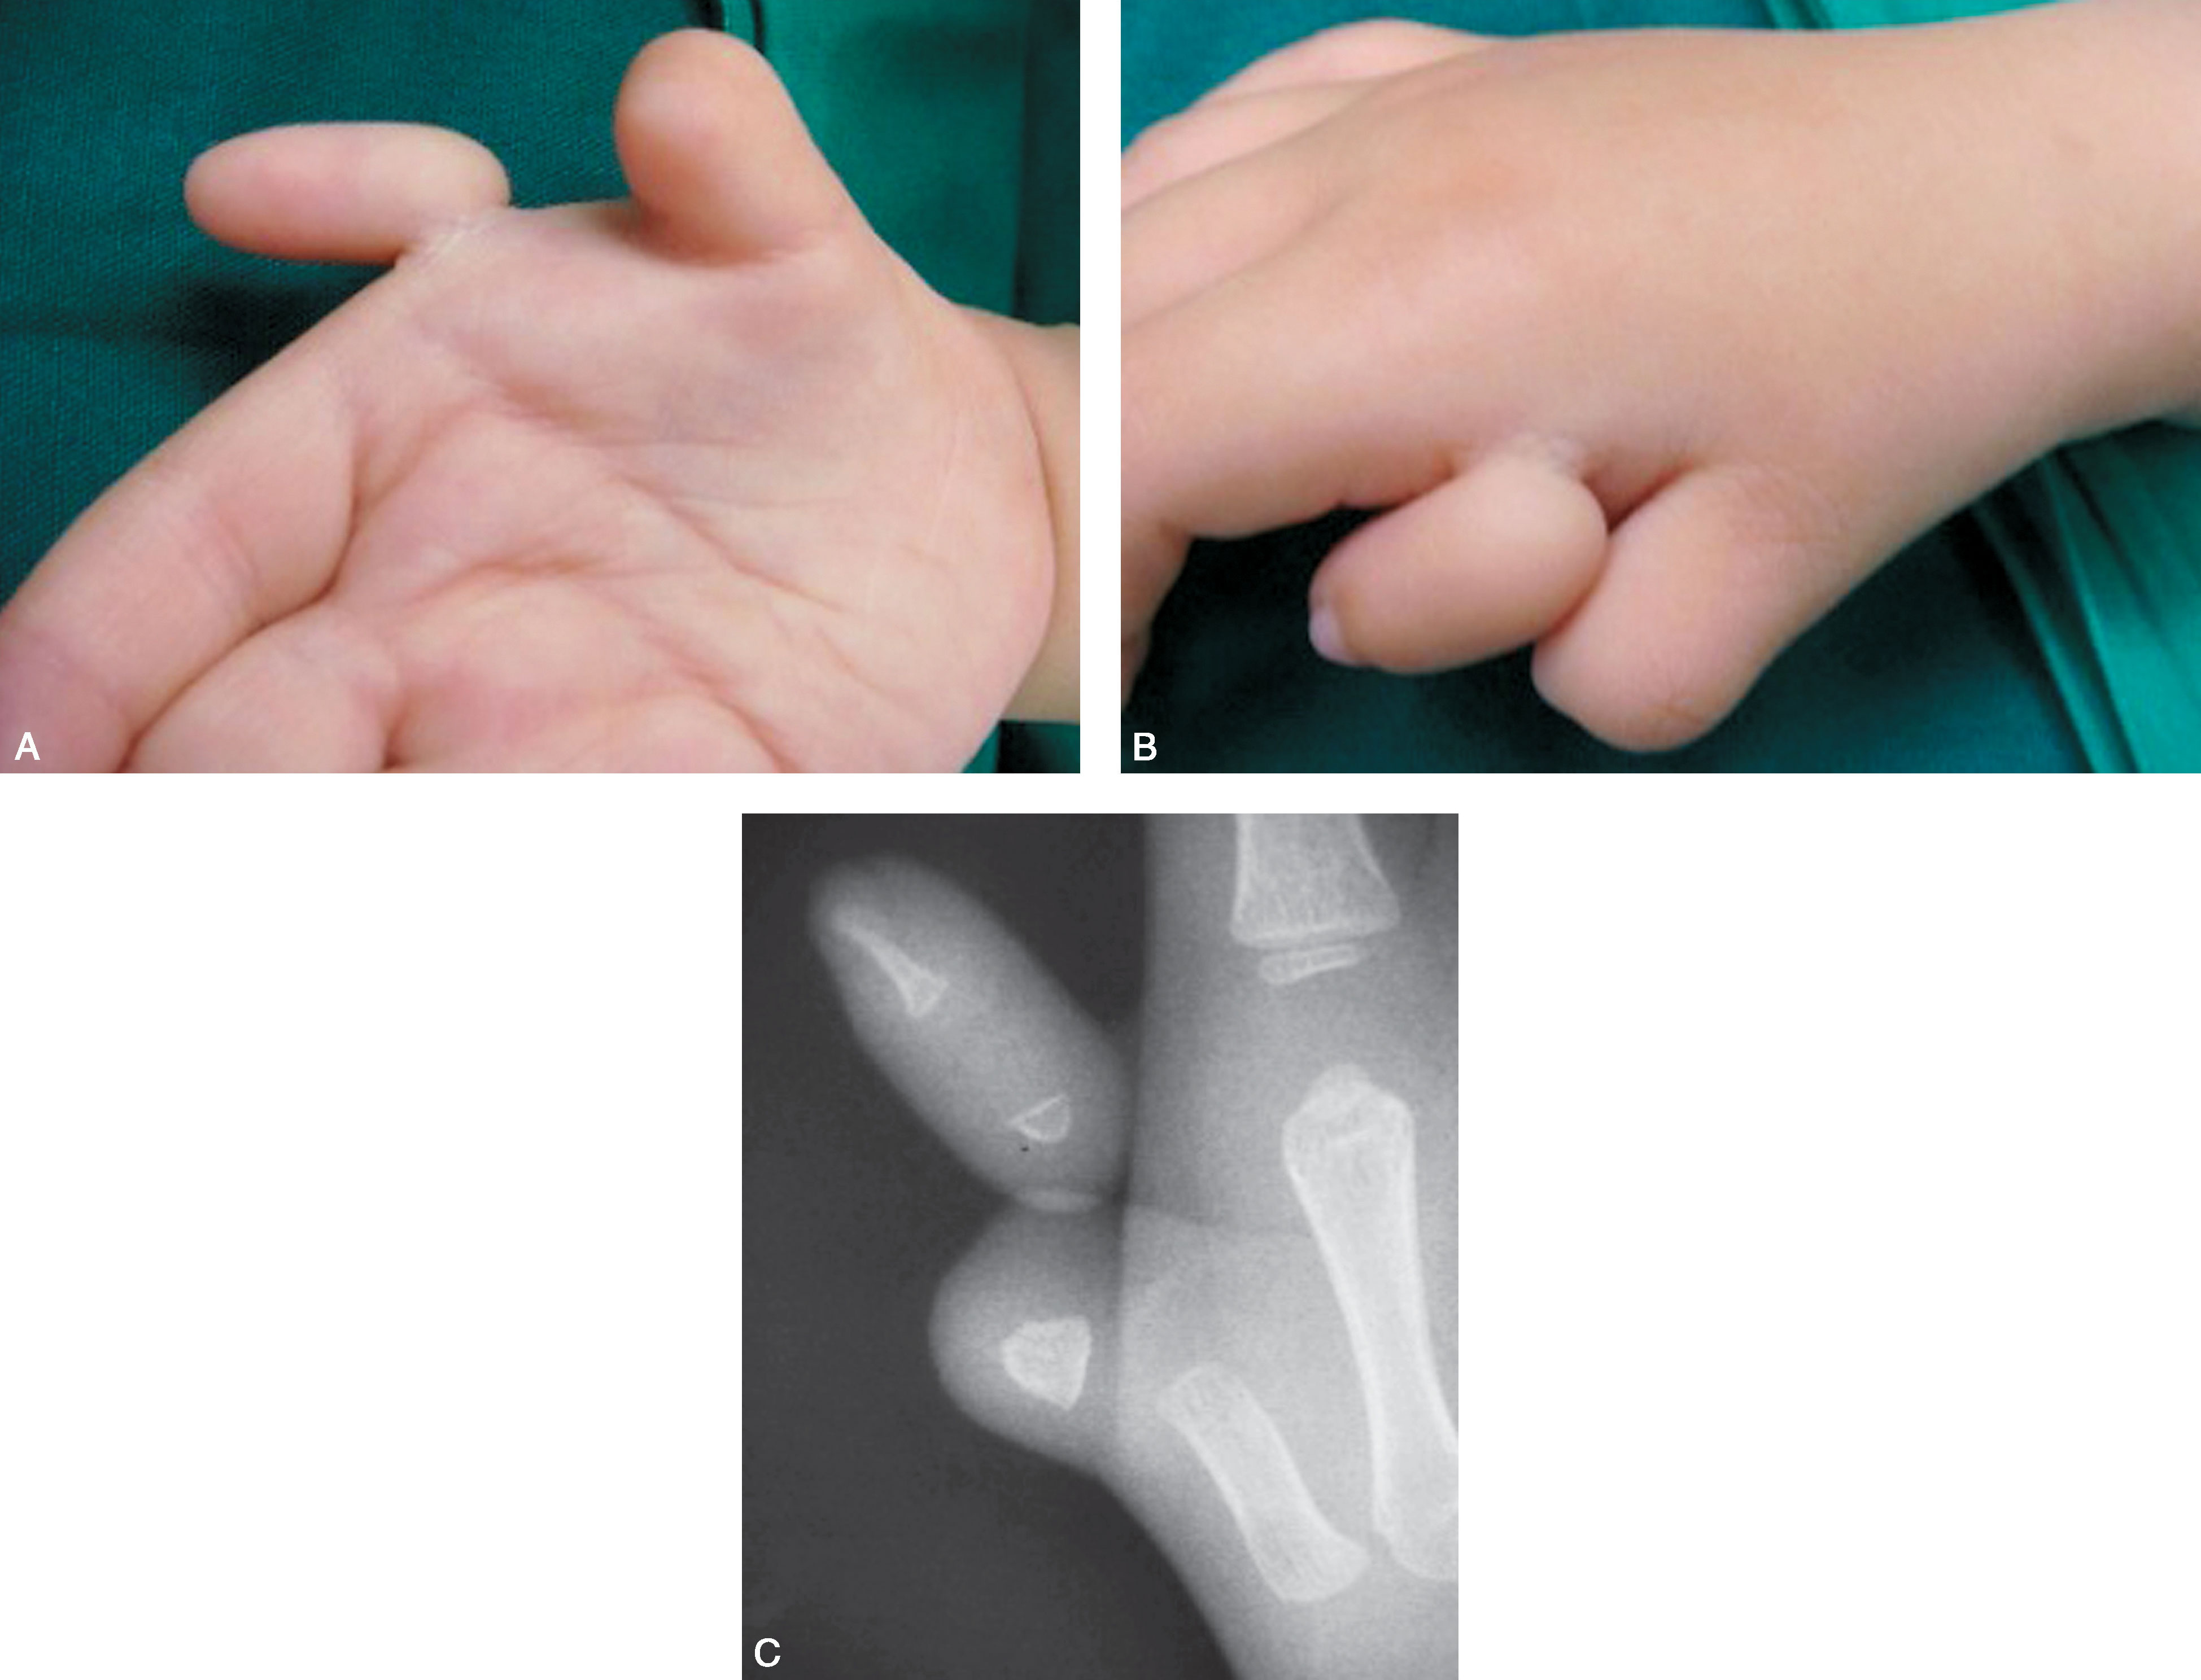

图2-1-11 Ⅱ型病例7

A.主、次拇指外形及大小相差十分明显,指甲融合一起;B.掌侧面;C.X 线片显示桡侧拇指远节指骨仅为细小骨片,选择治疗较为容易,切除桡侧拇指后需重建甲沟,保留的尺侧拇指力线好,不需要截骨